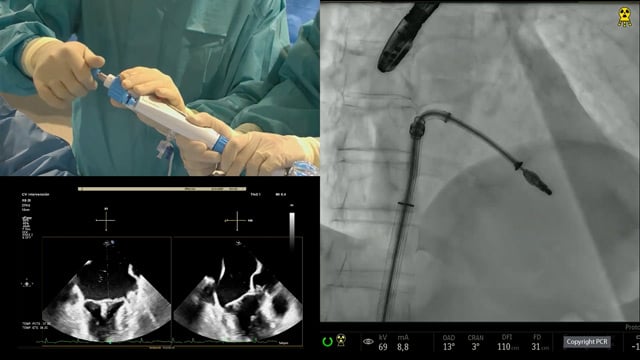

Looking at the heart and the brain - What is the role of LAA closure?

18 May 2022 – From EuroPCR 2022

Based on a pre-registered case study of a 68-year-old male patient, DG, who presented with atrial fibrillation, intracranial bleeding on warfarin, and compartment syndrome secondary to bleeding from warfarin, this EuroPCR 2022 session will allow you to discuss the challenges of treating AF patients with previous intracranial...